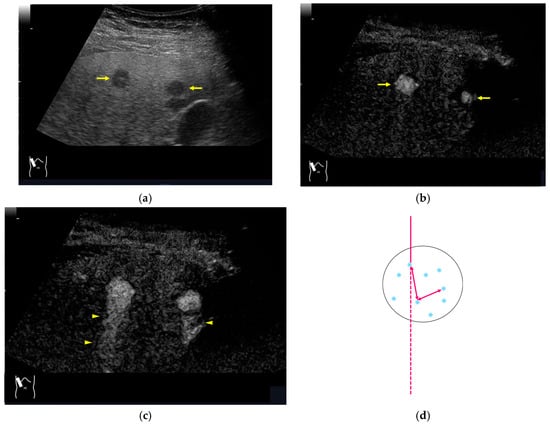

Figure 13.

Prolonged hyperenhancement. (a) CEUS image in the postvascular phase. Hyperenhanced areas (arrows). (b) Superb microvascular imaging reveals many aggregated bubbles passing in the portal vein (arrows).

Figure 14.

Posterior echo enhancement appearing during CEUS. (a) Gray-scale US of the case (arrows). (b) CEUS image of the lesion (focal nodular hyperplasia) (arrows). (c) CEUS image of posterior enhancement (arrow heads). Posterior echo enhancement appears immediately after the mass is rapidly and homogeneously enhanced. (d) Reasonable explanation of this phenomenon. Many scattered signals emitted from the bubbles that rapidly enter the mass lesion interfere with each other inside the stained area, and these scattered signals return to the transducer with a certain time-delay. These time-delayed signals are displayed as a PEE. Black circle: mass lesion; small blue circles: CEUS bubbles; red solid line: ultrasound beam; red dashed line: ultrasound is expected to travel; red arrows: reflection between bubbles.